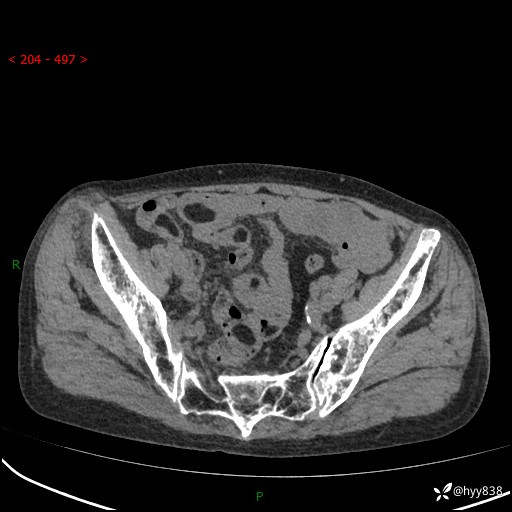

全腹部CT平扫